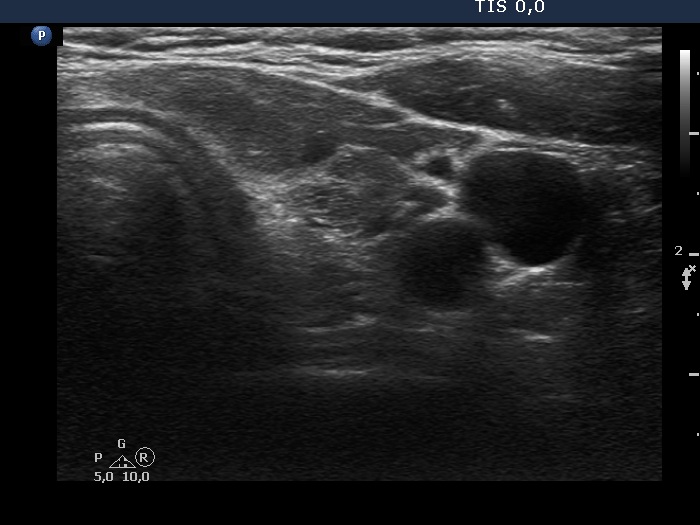

Ultrasonography. The thyroid was minimally hypoechoic and has several discrete lesions. A hypoechoic one in the left lobe showed both taller-than-wide and taller-than-long shape. There was a dominantly solid nodule in the lower part of the right lobe. There was a hypoechoic nodule in the upper, ventromedial part of the left lobe. This was the only lesion which was larger than 1 cm. This had a bit elongated hyperechoic figure.